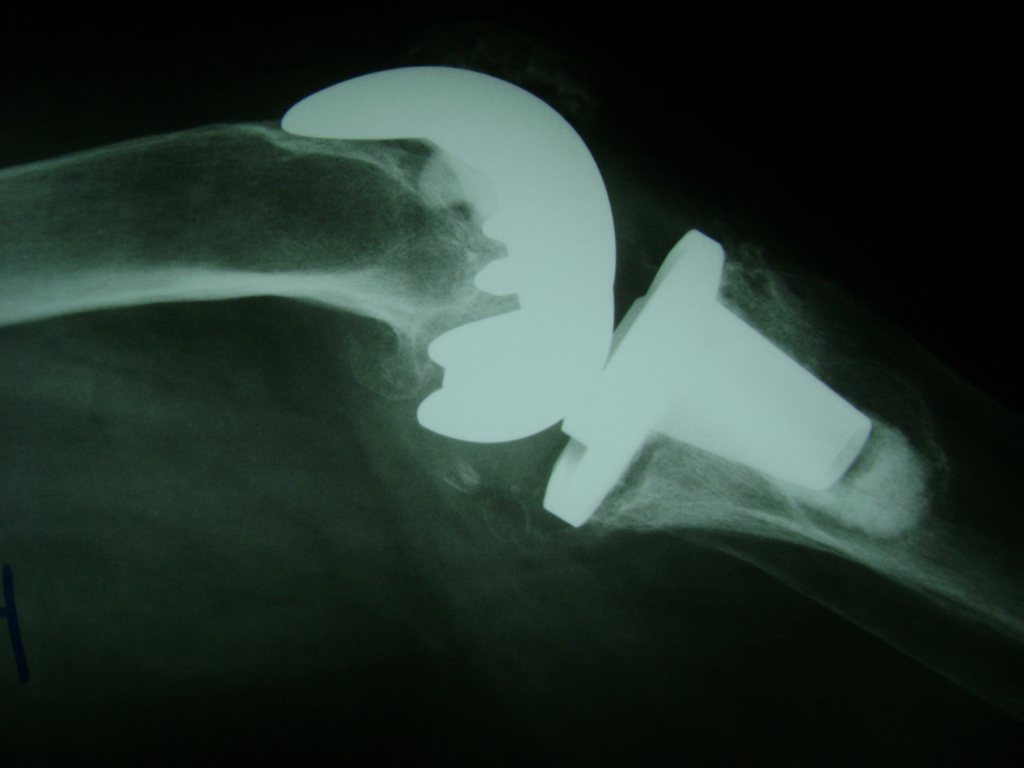

Cirugías de Hombros - Rodilla